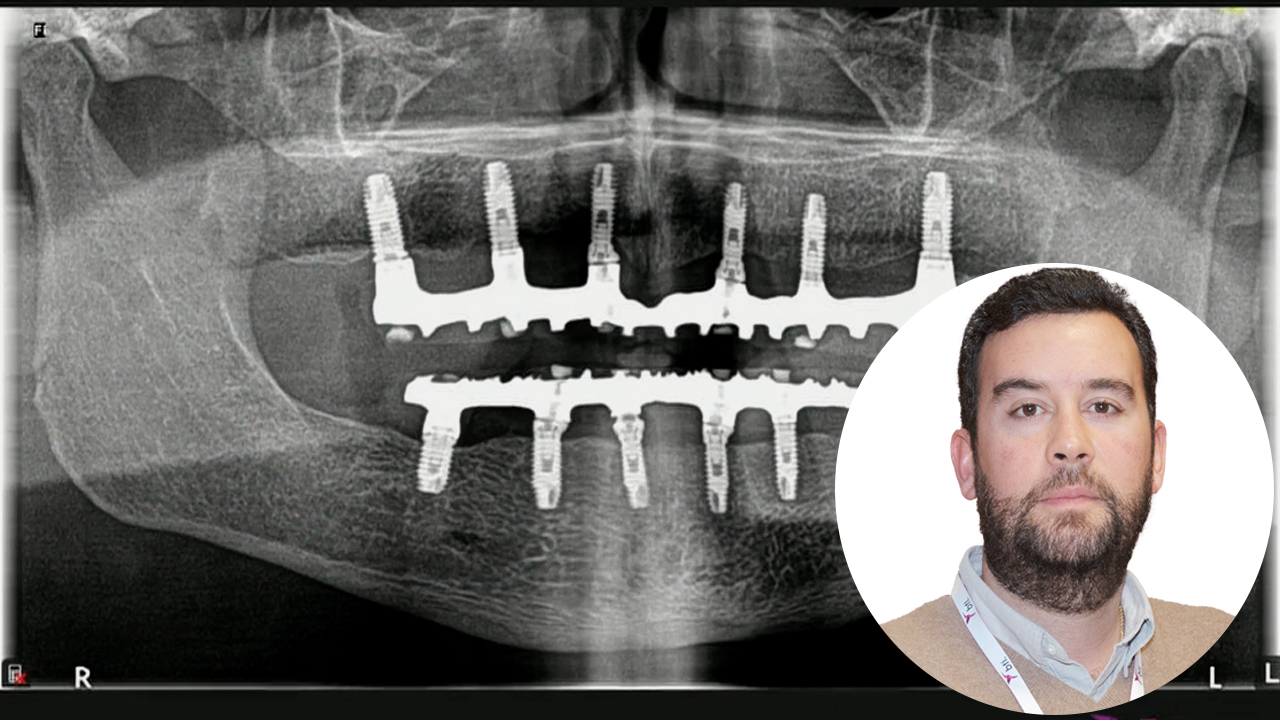

BTI Channel